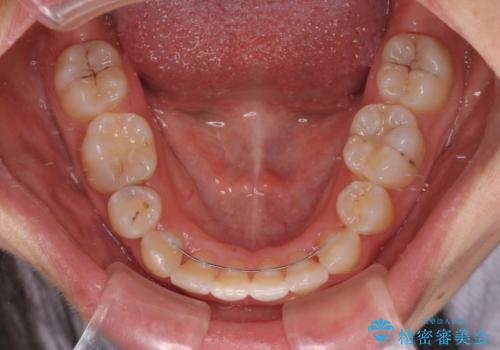

- 上下前歯のデコボコを気にして来院された患者様です。

口元の突出感はあまりなかったものの、デコボコを非抜歯で改善すると出っ歯になる可能性があるため、上下左右の第一小臼歯4本を抜歯し、ワイヤー装置にて矯正治療を行うこととしました。

口元の突出感がない分、奥歯を前方に移動させる必要がありましたが、予定の2年間で無事に治療を終えることができました。